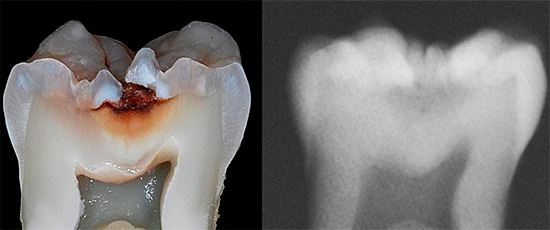

La foto sotto mostra un esempio di carie da fessure. Nei punti più profondi delle fessure, sono chiaramente visibili le aree scure dello smalto, sotto le quali si trovano le principali aree di danno dentale:

La seguente foto mostra chiaramente che la carie delle fessure è localizzata principalmente nella parte centrale della superficie masticatoria del dente. Se la malattia non è iniziata, la radice e il collo non sono interessati:

Il quadro clinico della nosologia consiste precisamente nella colorazione e nell'ulteriore distruzione dello smalto nell'area della fessura.